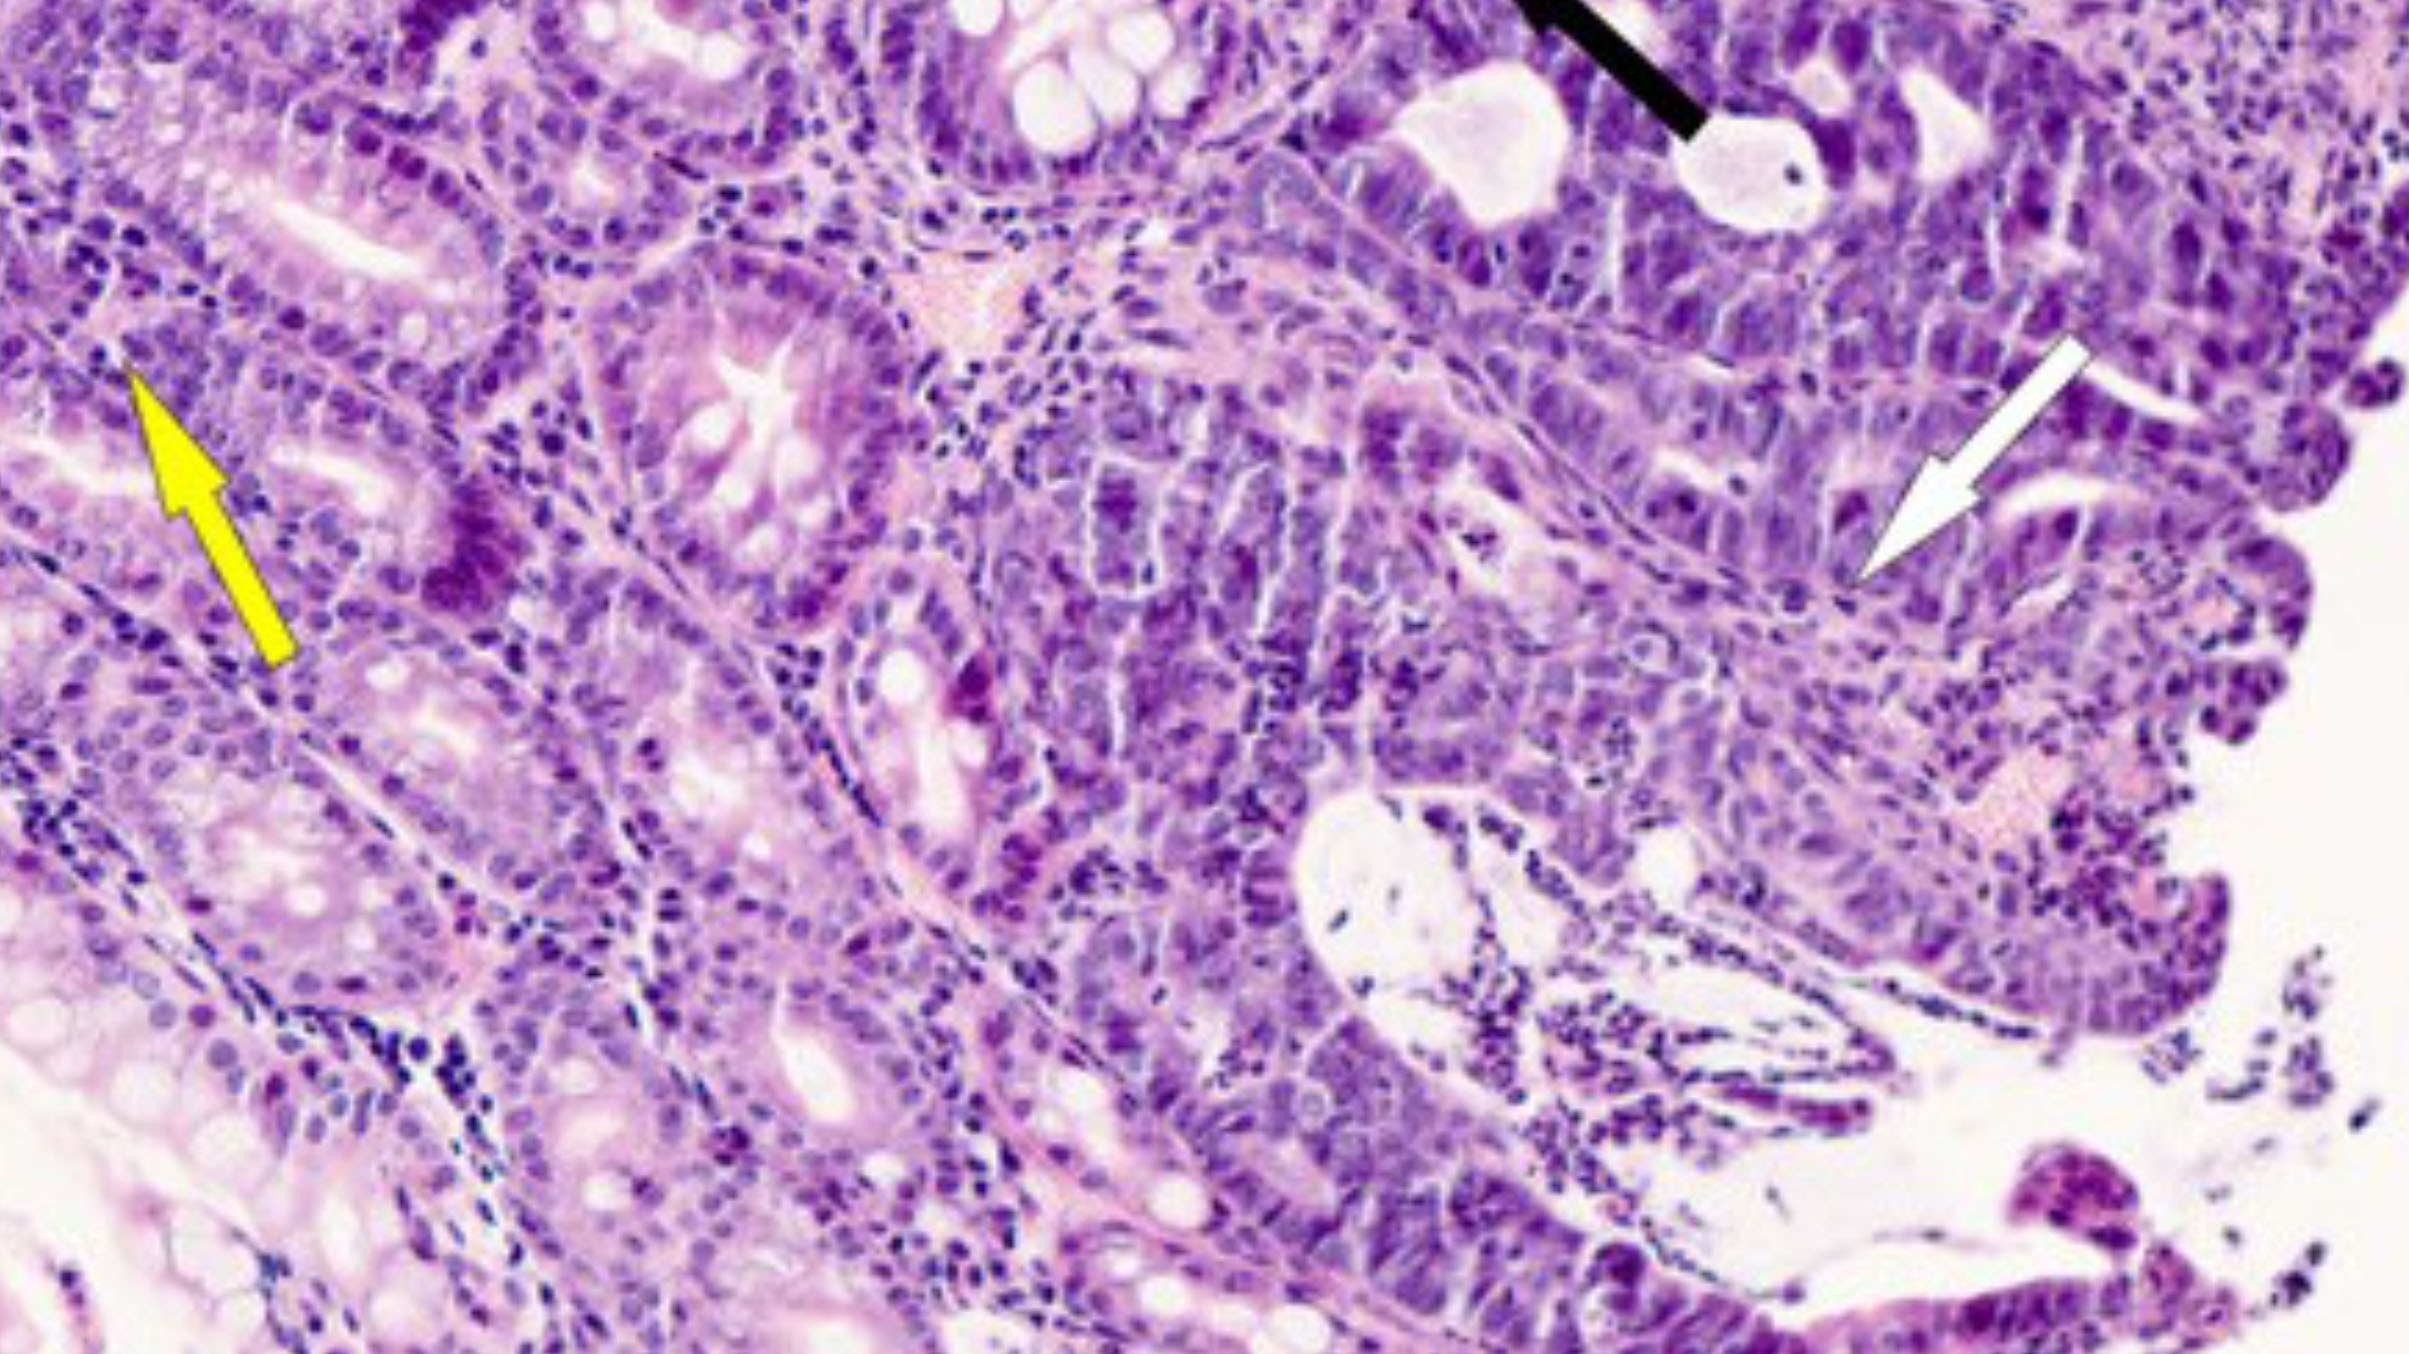

Образцы ткани толстой кишки с новообразованиями у устойчивых (А) и чувствительных (В) к гипоксии мышей. Источник: Dzhalilova et al. / PeerJ, 2025

Анализ показал, что у чувствительных к гипоксии мышей опухоли были примерно в три раза крупнее, чем у устойчивых. Кроме того, у этой группы в крови и в лимфатических узлах было больше В- и Т-лимфоцитов — защитных иммунных клеток, — а сами лимфатические узлы оказались крупнее. В селезенке чувствительных мышей были увеличены области, в которых формируются новые лимфоциты. Все это говорит о том, что у восприимчивых к недостатку кислорода мышей в ответ на развитие опухоли активировался более сильный иммунный ответ, который, однако, оказался неэффективен против новообразований. Это может быть связано с тем, что иммунные клетки у чувствительных грызунов были дисфункциональными — проявляли нарушенные функции. То есть, хоть их число и было увеличено, они работали неправильно.